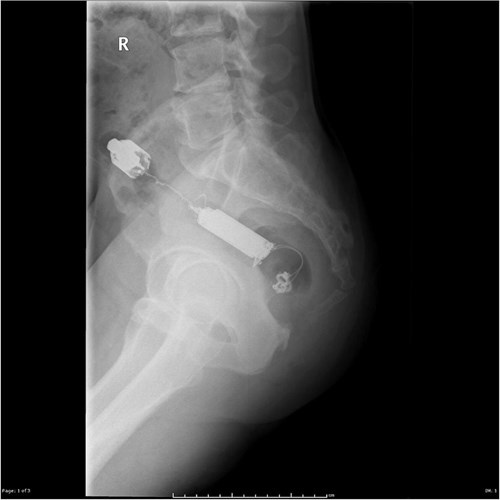

| Một phụ nữ 38 tuổi sống tại Scotland đã chung sống với đồ chơi tình dục trong cơ thể mình suốt 10 năm mà không hề hay biết. |